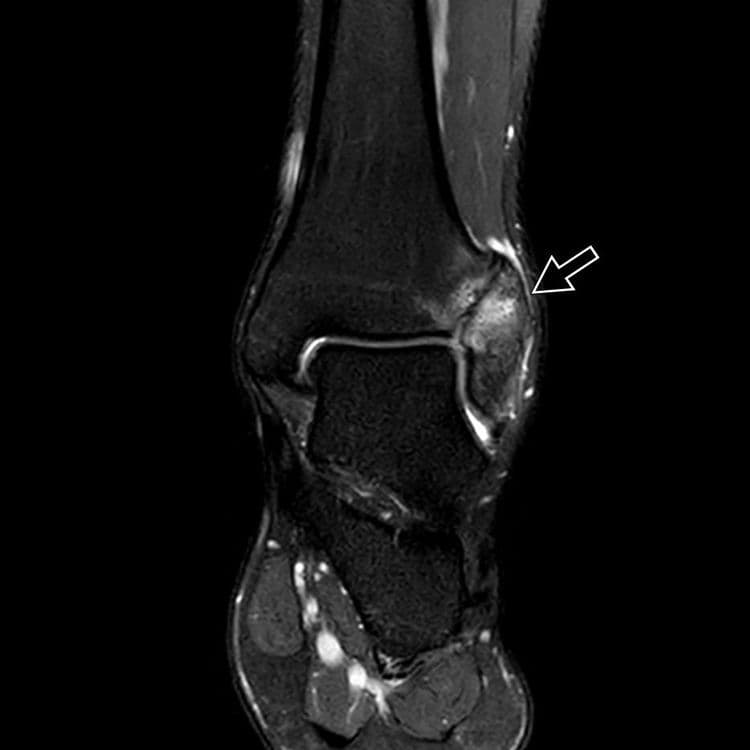

Complication rare des entorses graves de la syndesmose tibio-fibulaire inférieure.

MRI